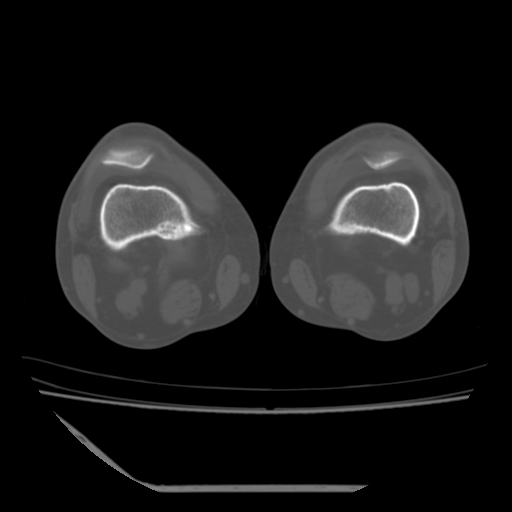

标题: CT13225:老年男性,左膝关节疼痛数月;请各位老师讨论。 [打印本页]

标题: CT13225:老年男性,左膝关节疼痛数月;请各位老师讨论。

骨质增生,骨性关节面硬化,关节积液,考虑退行性骨关节病

关节腔内少量积液,关节面退变。

双膝退变

骨质增生,骨性关节面硬化,关节间隙失常,关节积液,考虑退行性骨关节病.

骨质增生,骨性关节面硬化,关节积液,考虑退行性骨关节病。

这个病例诊断:退行性骨关节炎